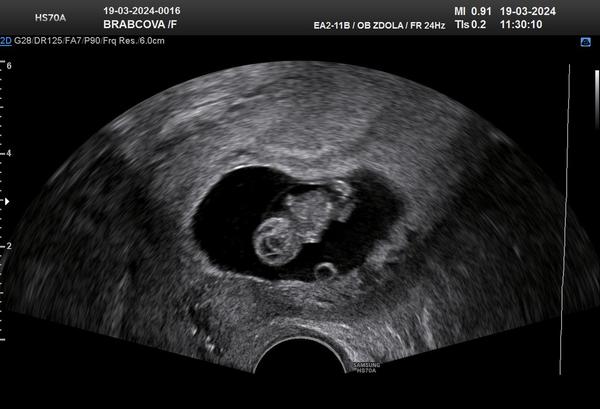

@brabechanule krásná fotečka❤️